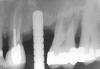

After penetration into the sinus is achieved, a sterile amalgam carrier is used two times to deliver a radiopaque bone substitute into the osteotomy. Then the osteotome used to infracture the subantral floor is lubricated with saline and inserted into the osteotomy until the stop on the osteotome reaches the alveolar crest. This pushes the bone substitute up under the sinus membrane and elevates it. Two more carriers of bone substitute are delivered in the same manner. This will provide around 2 mm of bone height in the sinus (four carriers provide around 2 mm of bone height). A radiograph is then taken to verify that the membrane was elevated, and the bone graft should appear as a dome (Figure 4). If the sinus floor has not been penetrated despite the impression that it was, the bone-graft material may have been pushed laterally. If this occurs, there will be no dome on the radiograph, but, rather, increased osseous density on the lateral aspect of the osteotomy. If this occurs the osteotomy needs to be deepened.

Figure 4  After infracturing the subantral wall with a 3.5-mm osteotome, bone was added and the presence of a dome was confirmed with a radiograph.

Figure 4